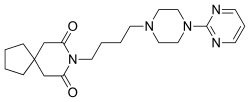

Tranquillanzien

Auch Buspiron, ein Partialagonist des 5-HT1A-Rezeptors, findet als Psychopharmakon zur Behandlung generalisierter Angststörungen Anwendung. In seiner Wirkung unterscheidet sich Buspiron von anderen Angstlösern (Anxiolytika), die vorrangig nicht das Serotoninsystem, sondern die Rezeptoren des Neurotransmitters γ-Aminobuttersäure (GABA) zum Ziel haben.